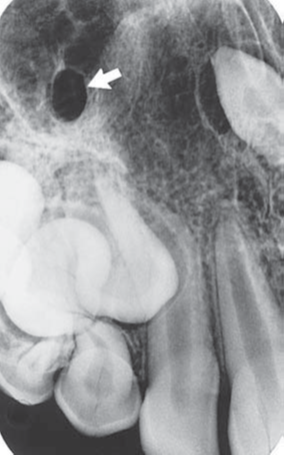

2) Identify the multiple asymptomatic radiopacities below the lower border of mandible. Patient was 45 years old and suffered from Tuberculosis in the past.